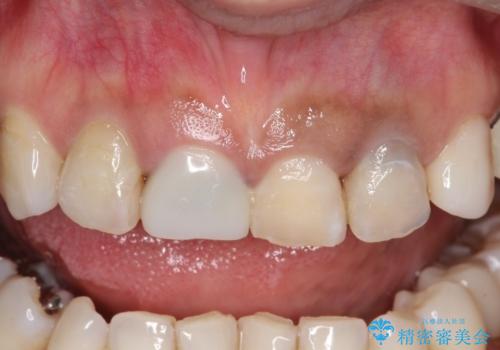

【オールセラミッククラウン】前歯を白くきれいにしたい。

- 前歯の変色を主訴に来院されました。

歯茎のラインも整っていなかったため、手術を行いきれいな被せ物をいれることができました。